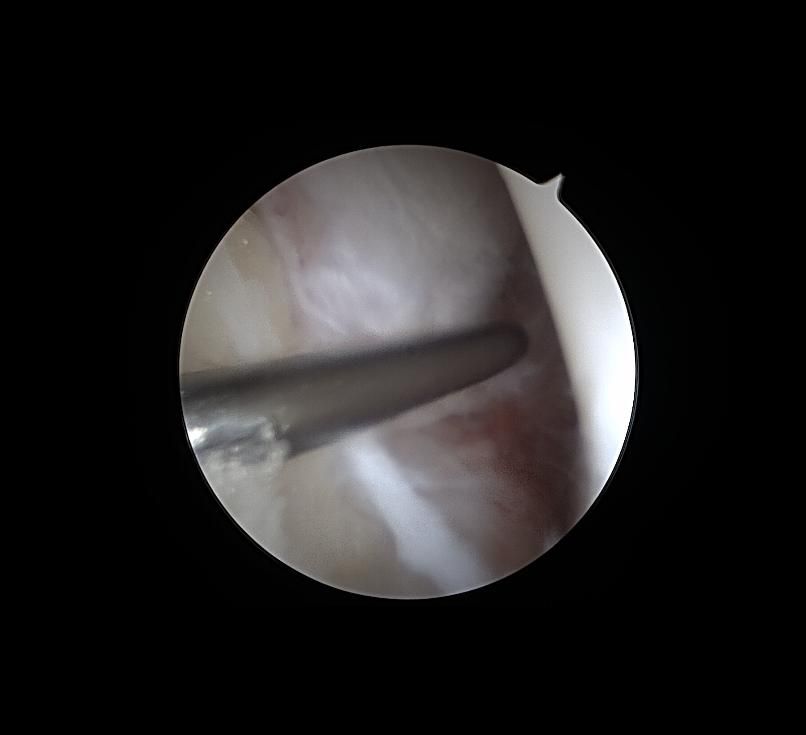

제가 발목 연골손상이라 mri와 내시경 사진이 있는데

어떤 상태인지 좀 다른 고견을 들어보고자 합니다

• 1번 째 사진

발목 연골 손상은 정도에 따라 회복 가능성 차이가 크고 mri와 내시경 소견이 매우 중요해요 완전 손상보단 부분 손상이면 재활과 치료로 걷기와 가벼운 운동은 충분히 가능할 수 있어요 이미지 확인은 병원에 내원 하셔서 정확한 진단을 받으시길 바랍니다!

현재 연골 손상이 있으신 것으로 보이는데요, 올려주신 사진이 참고에 도움이 될 수 있으나 정확한 소견을 말씀드리기에는 어려움이 있으므로 정확한 소견은 주치의에게 들어보시는 것이 좋겠습니다.